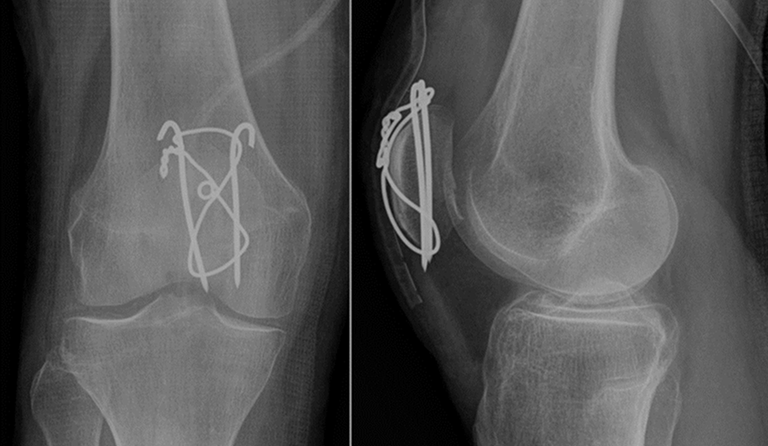

- Quirúrgico: Es necesario en casos donde la fractura compromete la función de extensión. Incluye la reconstrucción rotuliana mediante cirugía.